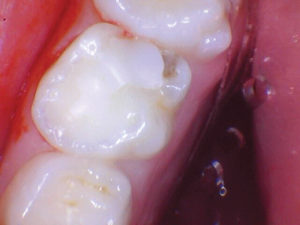

Figura 7. Después del ataque

con ácido y el uso del agente de unión Scotchbond Universal (3M), los dos

molares primarios superiores se restauraron con Activa Bioactive Restorative

A2. |